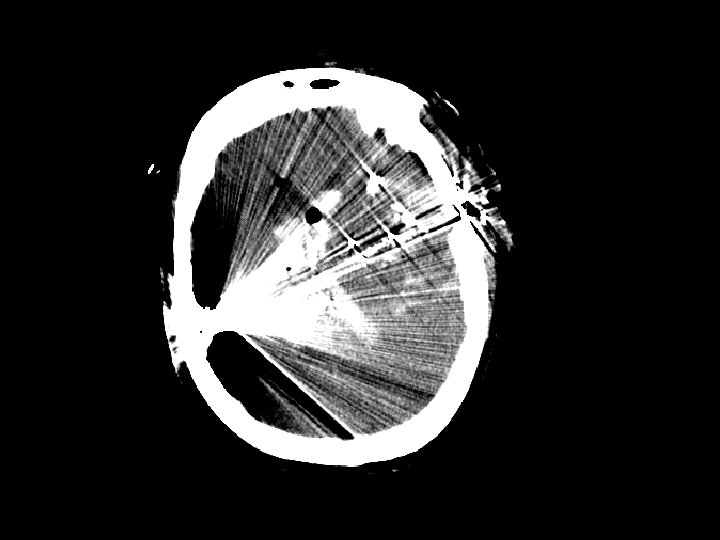

Tổn thương sợi trục lan tỏa • Lực xé và xoay làm gián đoạn hệ thống sợi trục • Cơ chế: chấn thương do tăng tốc và giảm tốc đột ngột • Chẩn đoán hình ảnh – Không rõ qua CT – MRI thể hiện rõ mức độ tổn thương • Không có biện pháp điều trị đặc hiệu • Có thể gây các tổn thương thần kinh trên bệnh nhân có CT bình thường nhưng tổn thương nặng